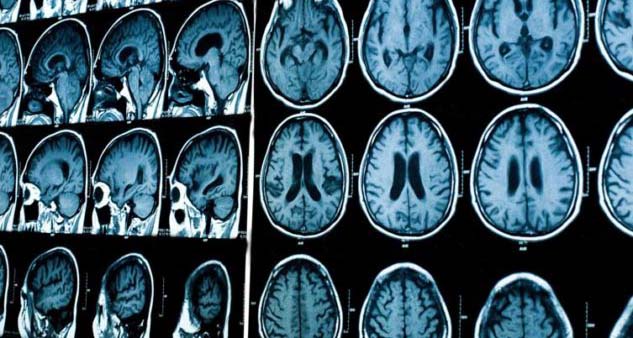

Hμερίδα με θέμα το αγγειακό εγκεφαλικό επεισόδιο διοργανώνεται από το Πανεπιστημιακό Nοσοκομείο Λάρισας την Παρασκευή 23 Ιανουαρίου στην Ιατρική Σχολή του Πανεπιστημίου Θεσσαλίας.

Αφετηρία για την ημερίδα αποτελεί η τριετής λειτουργία της Επεμβατικής Νευροακτινολογίας του ακτινολογικού εργαστηρίου του Πανεπιστημιακού Νοσοκομείου Λάρισας, η οποία συμμετέχει στην διαχείριση ασθενών με αγγειακό εγκεφαλικό επεισόδιο με την θεραπευτική δυνατότητα της μηχανικής θρομβεκτομής.